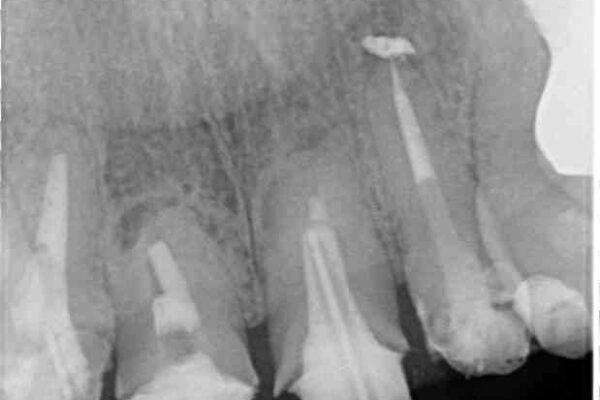

仮歯が不適合で歯肉が腫脹していたため、しっかりと調整した新しい仮歯にして腫れを改善した上で、オールセラミッククラウンにて補綴することとしました。

治療前

• 仮歯のまま放置した前歯 オールセラミッククラウンで自然な前歯に 治療前画像